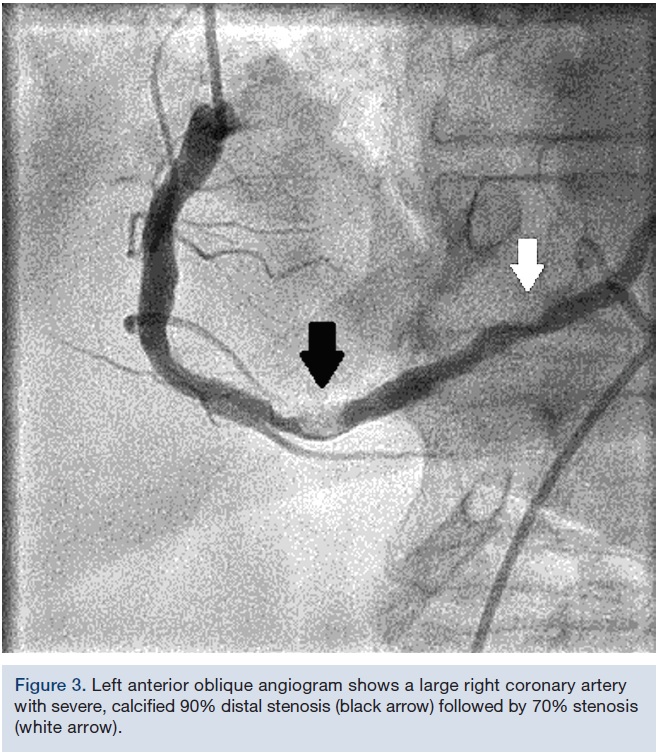

An 81-year-old female continued to experience effort angina with activities of daily living in spite of optimal medical therapy. She had a PCI of her left anterior descending artery (LAD) and obtuse marginal branch (OM) 7 years prior. Medications included aspirin, metoprolol, amlodipine, rosuvastatin, furosemide, and sublingual nitroglycerine. Cardiovascular examination was unremarkable except for a grade 2/6 systolic murmur at the left sternal border, radiating to the carotid arteries. Electrocardiogram (EKG) showed sinus rhythm with first-degree atrioventricular block. An echocardiogram revealed preserved left ventricular function with mild aortic stenosis. Coronary angiogram showed patent stents and mild non-obstructive disease in the left system. A large, severely tortuous, fully calcified right coronary artery (RCA) was noted to have a 90% distal stenosis followed by a 70% lesion (Figure 3).